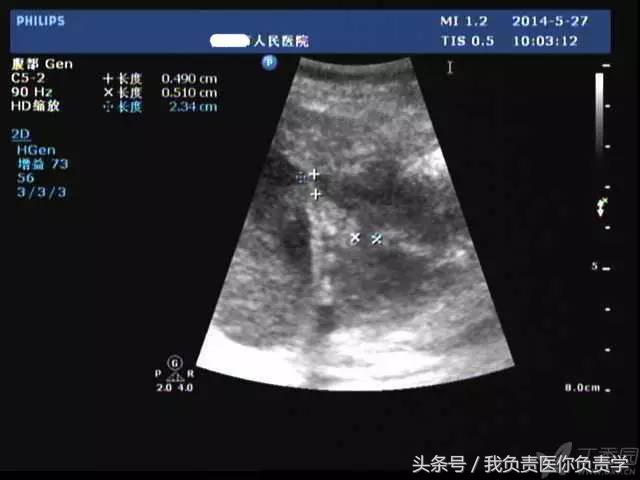

患者女,79岁,晚餐后出现脐周疼痛数小时急诊。患者无发热,实验室检查示白细胞14×109/L,临床考虑阑尾炎,行超声检查所见如下:

图2为高频探头所见,示胆囊壁肝床侧回声中断,周围可见无回声分布

超声诊断为胆囊穿孔,后经手术证实。